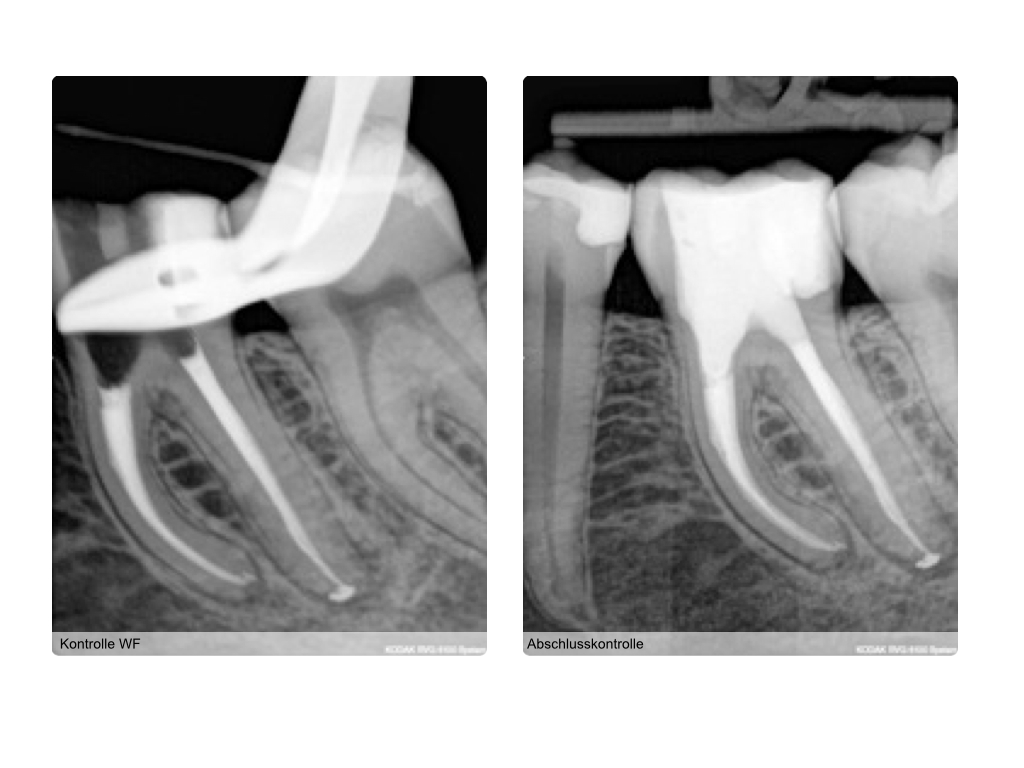

WS4.004

Instrumentenfrakturen (1)